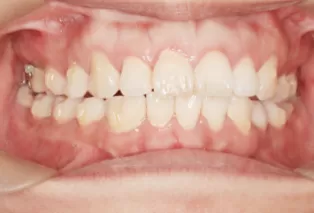

Intraoral photos